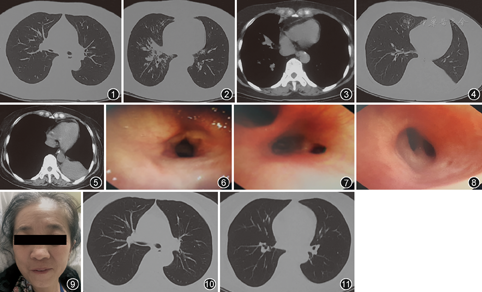

2018年12月3日喉镜检查(外院):咽部充血,会厌光滑,双侧声带肿胀,表面白色样物(分泌物?),活动好,闭合差,双侧梨涡分泌物多,未见明显新生物。血气分析:pH值为7.5,PaO2为72 mmHg(1 mmHg=0.133 kPa),PaCO2为34.8 mmHg,K+为2.99 mmol/L,Na+为109 mmol/L;K+为3.64 mmol/L,Na+为129 mmol/L。胸部CT示右肺中、下叶感染性病变(下叶为著),并右肺下叶基底段支气管内黏液嵌塞,右肺中叶及下叶支气管轻度扩张(图1,图2,图3)。

入院查体:体温36 ℃,脉搏99次/min,呼吸23次/min,血压162/81 mmHg,意识清,端坐位,精神差,听诊双肺呼吸音粗,双肺可闻及哮鸣音。入院后化验血常规:白细胞为9.1×109/L,中性粒细胞占0.83;降钙素原为0.32 μg/L。给予解痉平喘、祛痰、抗感染、甲泼尼龙琥珀酸钠80 mg/d、纠正电解质紊乱等对症治疗。于2018年12月14日中午患者突发吸气样呼吸困难,当时心率为152次/min,血压为189/114 mmHg,经皮血氧饱和度为98%(鼻导管吸氧3 L/min),先后给予地塞米松、西地兰、呋塞米、布地奈德高压泵雾化吸入等治疗,患者症状稍缓解。3 h后突发意识障碍,急查血气分析示PaCO2为80.3 mmHg,考虑合并急性二氧化碳潴留、肺性脑病,建议转我科重症监护室行气管插管,因患者声门狭窄、声带水肿明显,气管插管困难,但最终插管成功(5.5号气管插管),连接有创呼吸机辅助呼吸。约1 h后患者意识转清。复查血常规:白细胞为11.6×109/L,中性粒细胞占0.85;降钙素原为13.7 μg/L;ESR为11 mm/1 h;C反应蛋白为33.2 mg/L。给予抗感染、甲泼尼龙琥珀酸钠80 mg/d、解痉平喘、纠正电解质乱、营养支持等对症治疗,患者病情逐渐好转,于2018年12月27日拔除气管插管。复查血常规:白细胞为16.7×109/L,中性粒细胞占0.86;降钙素原为0.05 μg/L。复查喉镜示室带肥厚,声带黏膜略增厚,活动可。复查胸部CT示左肺下叶不张,右肺病灶完全吸收,新发左肺不张(图4,图5)。鼻窦CT示外鼻轻度塌陷,鼻中隔略向右偏,双侧下鼻甲肥大,左侧上颌窦炎。患者拔除气管插管后序贯经鼻高流量加温加湿装置吸氧,咳嗽、气短症状明显减轻,诉咽部不适,声音嘶哑,痰量中等,不易咳出,生命体征平稳,听诊双肺呼吸音粗,双肺可闻及少量干湿性啰音。

患者声门狭窄原因不明确,因当时气管插管管径过细,气管镜无法进入,于2019年1月10日(拔除气管插管2周)行支气管镜检查,镜下见声门水肿,略狭窄,闭合欠佳,活动差,气管软骨环显示不清,呼气相气管塌陷、略狭窄,右中间支气管开口明显狭窄,尤以呼气相明显,考虑为中间支气管塌陷所致(图6,图7,图8)。查体可见马鞍鼻(图9),结合气管镜下表现及相关化验检查,考虑为RP,请风湿科会诊后加用甲氨蝶呤(10 mg,1次/周)联合糖皮质激素治疗。2019年1月16日复查胸部CT示左肺病灶吸收,双肺未见明显异常(图10,图11)。患者一般状况好转后出院,继续口服甲泼尼龙16 mg,1次/d及甲氨蝶呤10 mg,1次/周。